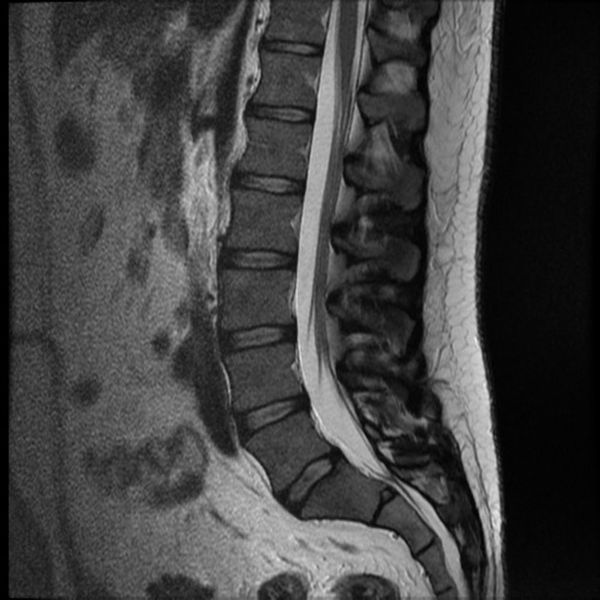

Магнитно-резонансное изображение нормального состояния поясничного отдела позвоночника